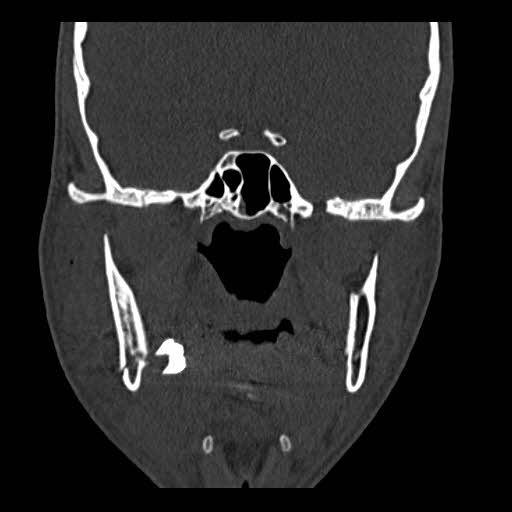

This case could remind surgeons to consider the possibility of displacement of the impacted third molar in the fractured line to adjacent spaces, during open reduction and internal fixation of mandibular angle fracture.

该病例可提醒外科医生,在下颌角骨折切开复位内固定术中,要考虑到阻生第三磨牙在骨折线处移位至相邻间隙的可能性。